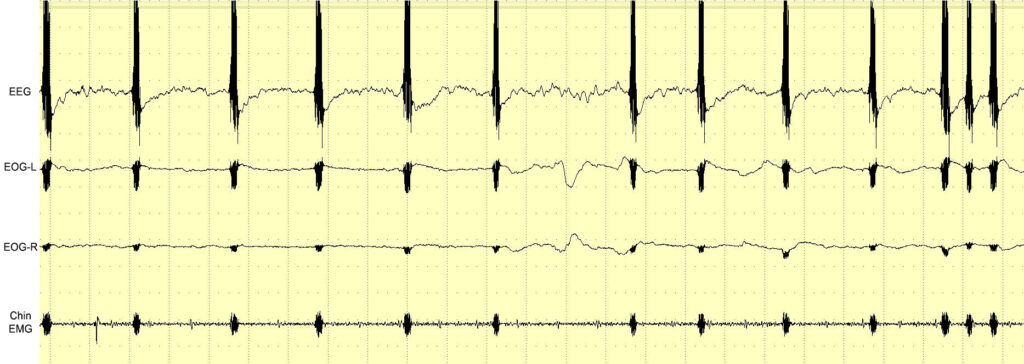

As humans spend one-third of their lives asleep, many studies have explored the possibility of controlling dreams. For the first time, we tested electrical brain stimulation (EBS) of the motor cortex during REM sleep to observe how it is incorporated into dreams. Electrodes were implanted in the motor cortex of one man with the ability to induce lucid dreams (LDs). Under polysomnographic (PSG) observation, the cortex was stimulated by an alternating current during REM sleep, sleep paralysis (SP), and lucid dreams (LDs). The results show that, within a certain current range, EBS did not wake the participant. Though he could not recall specific motor stimulations in REM sleep, some irregular changes in dream plots were observed. The most interesting results were observed during an LD in which it was possible to intentionally observe an EBS-induced contraction, which interacted with a dream object. In some cases, sensory feedback from the EBS of the motor cortex was perceived when the PSG data showed REM sleep and muscle atonia. Though some of the results need further confirmation, we discuss how the obtained data could present new horizons for controlling dream scenes and inducing LDs.

Testing in wakefulness and in dreams

Results